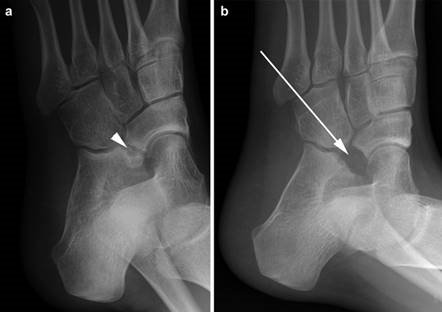

Weight-bearing anteroposterior (AP), lateral, and sesamoid axial radiographs are mandatory. On the AP view, the surgeon measures the Hallux Valgus Angle (HVA, normal < 15°), the Intermetatarsal Angle (IMA, normal < 9°), and the Distal Metatarsal Articular Angle (DMAA). The lateral view is scrutinized for Meary's angle (talo-first metatarsal angle) to identify midfoot collapse, as well as the presence of dorsal osteophytes indicative of hallux rigidus. The sesamoid axial view is critical for assessing the degree of sesamoid subluxation and the integrity of the crista.

Clinical & Radiographic Imaging Archive